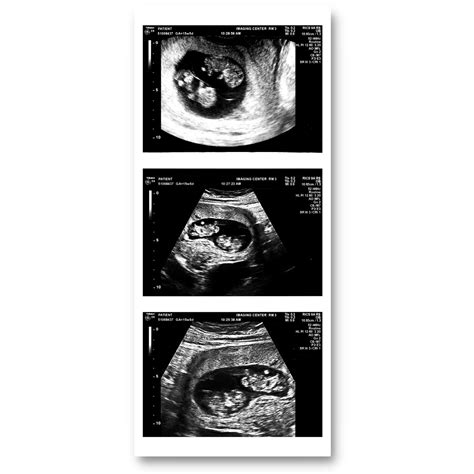

A 9 weeks pregnant ultrasound is typically performed to assess the baby's growth and development. At this stage, the ultrasound can provide detailed images of the fetus, allowing healthcare providers to measure the baby's size, check for a heartbeat, and evaluate the overall health of the pregnancy. This scan is usually done transabdominally, meaning the ultrasound probe is moved over your belly, or transvaginally, where the probe is inserted into the vagina for a clearer view.

• Detecting Multiple Pregnancies: It can help identify if you are carrying twins or multiples.

• Gestational Sac: A fluid-filled structure that contains the embryo.

• Yolk Sac: A small structure that produces blood cells and helps in the early development of the embryo.

• Embryo: The developing fetus, which should be visible and measurable.

• Heartbeat: A detectable heartbeat, which is a positive sign of a healthy pregnancy.

• Crown-Rump Length (CRL): The measurement from the top of the head to the bottom of the buttocks, which helps to estimate the baby's age and growth.